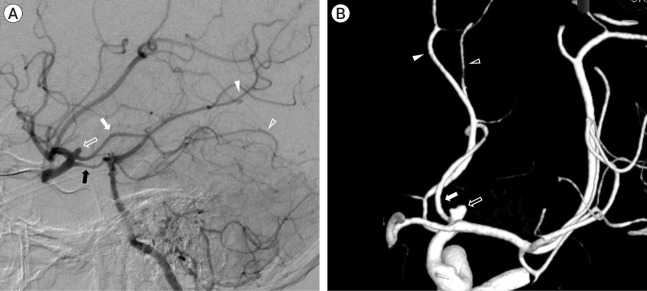

增生性脉络膜前动脉(AchA)是一种极为罕见的先天性血管变体,可被误认为是其他脑动脉。本病例报告介绍了一名38岁的男子,他表现出严重的突发性头痛,并被诊断为由增生性AchA引起的动脉瘤破裂。动脉瘤用线圈栓塞成功治疗,但8个月后发现复发,需要额外的手术干预。讨论强调了增生性AchA的分类,并强调了识别这种解剖变异以避免治疗过程中并发症的重要性。本病例报告强调了在脑动脉瘤治疗中对增生性AchA的认识和理解的必要性。

Hyperplastic anterior choroidal artery (AchA) is an extremely rare congenital vascular variant that can be mistaken for other cerebral arteries. This case report presents a 38-year-old man who presented with a severe sudden-onset headache and was diagnosed with a ruptured aneurysm originating from a hyperplastic AchA. The aneurysm was successfully treated with coil embolization, but recurrence was detected after eight months, leading to additional surgical intervention. The discussion highlights the classification of hyperplastic AchA and emphasizes the importance of recognizing this anatomical variant to avoid complications during treatment. This case report underscores the need for awareness and understanding of hyperplastic AchA in the management of cerebral aneurysms.